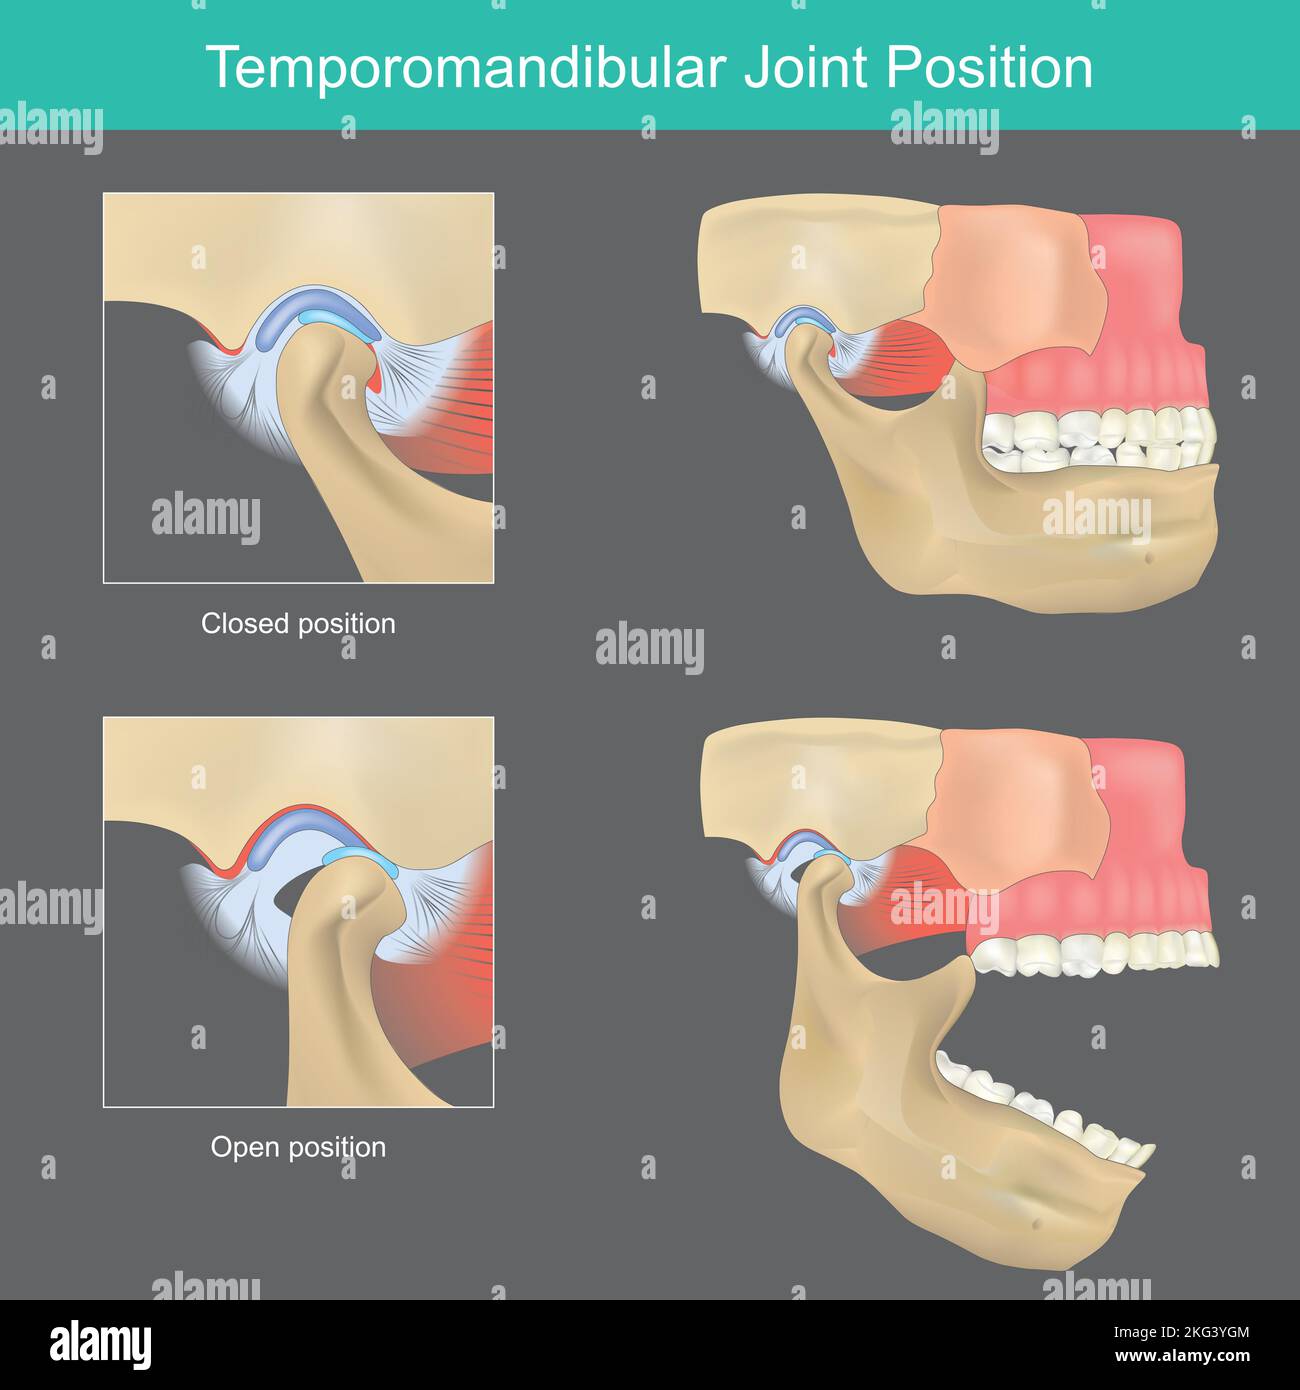

Posizione dell'articolazione temporomandibolare. Quando si apre la bocca, si agisce come una cerniera scorrevole, collegando la bacchetta al cranio. Illustrazione Vettorialehttps://www.alamy.it/image-license-details/?v=1https://www.alamy.it/posizione-dell-articolazione-temporomandibolare-quando-si-apre-la-bocca-si-agisce-come-una-cerniera-scorrevole-collegando-la-bacchetta-al-cranio-image491812292.html

Posizione dell'articolazione temporomandibolare. Quando si apre la bocca, si agisce come una cerniera scorrevole, collegando la bacchetta al cranio. Illustrazione Vettorialehttps://www.alamy.it/image-license-details/?v=1https://www.alamy.it/posizione-dell-articolazione-temporomandibolare-quando-si-apre-la-bocca-si-agisce-come-una-cerniera-scorrevole-collegando-la-bacchetta-al-cranio-image491812292.htmlRF2KG3YGM–Posizione dell'articolazione temporomandibolare. Quando si apre la bocca, si agisce come una cerniera scorrevole, collegando la bacchetta al cranio.